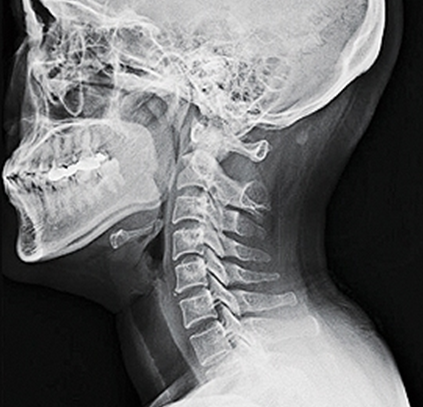

앞서 언급한 바와 같이 목의 자연적인 전만증은 경추를 안쪽으로 C자 모양으로 굽게 하는데, 그 곡률 정도가 20~40도 범위에 속하면 정상적이고 건강한 경추 전만증의 범위로 볼 수 있습니다. 만약 사람이 경추 전만증의 상실을 경험하고 그 정상 범위에 속하지 않는다면 이는 목이 지나치게 곧게 되었다는 것을 의미합니다.

밀리터리 넥(Military Neck)은 지나치게 곧은 목이 사람에게 줄 수 있는 외모, 즉 차렷 자세로 서 있는 전통적인 군사 자세를 말한다.

경추 전만증의 상실은 목이 지나치게 곧게 되었다는 것을 의미하며, 이는 앞으로 머리 자세 및 군사 목과 같은 여러 가지 문제를 일으킬 수 있습니다.